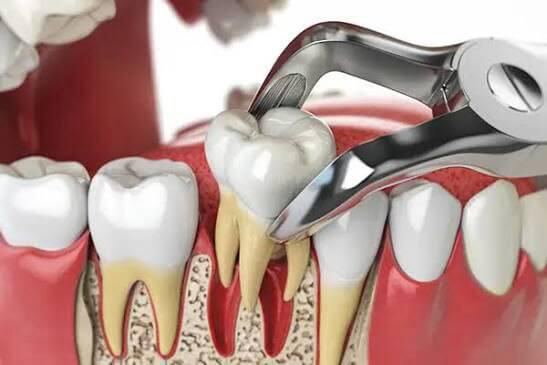

الخلع الجراحي للأسنان

إزالة الأسنان المكسورة أو المدفونة تحت اللثة، مثل ضروس العقل.

يعد خلع الأسنان، أو قلع الأسنان، جانبًا مهمًا من العناية بالأسنان عندما يتضرر أحد الأسنان بشكل كبير، إما بسبب العدوى الناتجة عن تسوس الأسنان أو الصدمة الناجمة عن طرق أو نتوء. في Kidz Smile، يجمع نهجنا في علاج الأسنان الخارجية بين الخبرة والتعاطف، مما يضمن حصول كل طفل على أفضل رعاية ممكنة مصممة خصيصًا لتلبية احتياجاته الخاصة.

- استكشاف البدائل: في حين أنه قد يوصى بخلع الأسنان في حالات الضرر الشديد، فإن فريقنا يستكشف علاجات بديلة كلما أمكن ذلك. وقد يشمل ذلك الإجراءات الترميمية، مثل تيجان الأسنان أو حشواتها، للحفاظ على بنية الأسنان الطبيعية.

- النهج اللطيف والرحيم: نهجنا في علاج الأسنان الخارجية يؤكد على اللطف والرحمة. نحن نعطي الأولوية لإدارة الألم ونستخدم تقنيات لتقليل الانزعاج، مما يضمن أن تكون التجربة إيجابية قدر الإمكان بالنسبة للطفل.